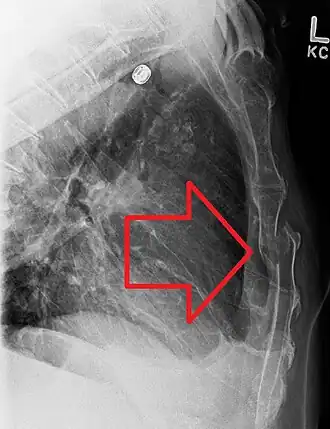

| Radiografia de tórax apresentando uma fratura esternal | |

As radiografias do tórax são realizadas em pessoas com trauma torácico e sintomas de fraturas do esterno, e podem ser seguidas por tomografia computadorizada.[13] Como as radiografias tiradas de frente podem não detectar a lesão, elas também são tiradas de lado.[14]